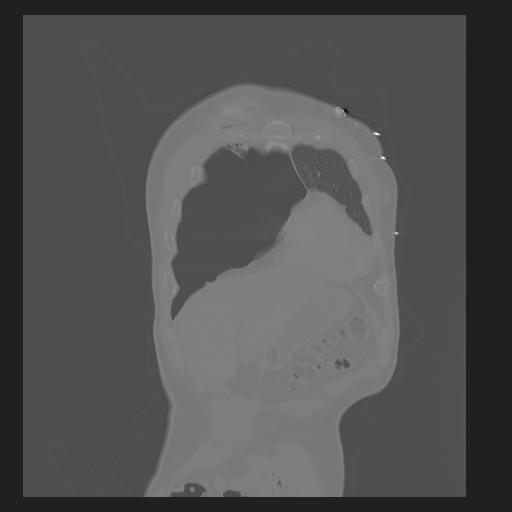

32 PULMON,CE,Coronal,3.000,PULMON,Coronal,